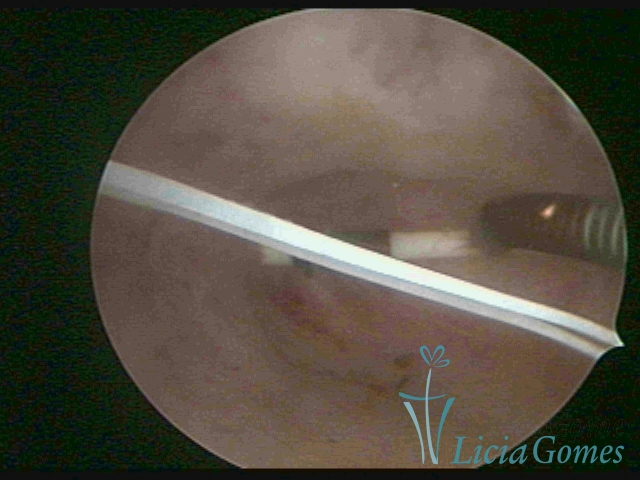

Uterine cavity with IUD and accumulated light mucus